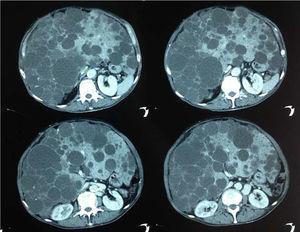

Varón de 70 años. Sin antecedentes personales ni familiares. Consulta por distensión abdominal y edema de miembros inferiores, simétrico, no gravitacionales, de años de evolución acompañado de anorexia y plenitud precoz. Examen físico: desnutrición proteico-calórica, ictericia de piel y mucosas. Abdomen con gran tumoración en hipocondrio derecho, dura, polilobulada e indolora. Miembros inferiores: edema hasta raíz de muslo, indoloro y sin signos fluxivos. La tomografía computarizada (TC) abdomen: hepatomegalia heterogénea. Múltiples quistes de aspecto simple sustituyendo casi la totalidad del parénquima. Uno de ellos comprime la vena cava y otro presenta contenido hemorrágico. Sin elementos de hipertensión portal. Riñones normales. Se realizó tratamiento médico con soporte nutricional y diuréticos. Dado el mal estado general del paciente no se planteó trasplante hepático ni resección parcial hepática. Se realizó punción transparietal guiada por TC de los 2 quistes de mayor tamaño, drenándose 600cc en total e instilación de alcohol. El paciente evolucionó bien con disminución de los edemas, mejoría del apetito y del estado nutricional (figs. 1 y 2).